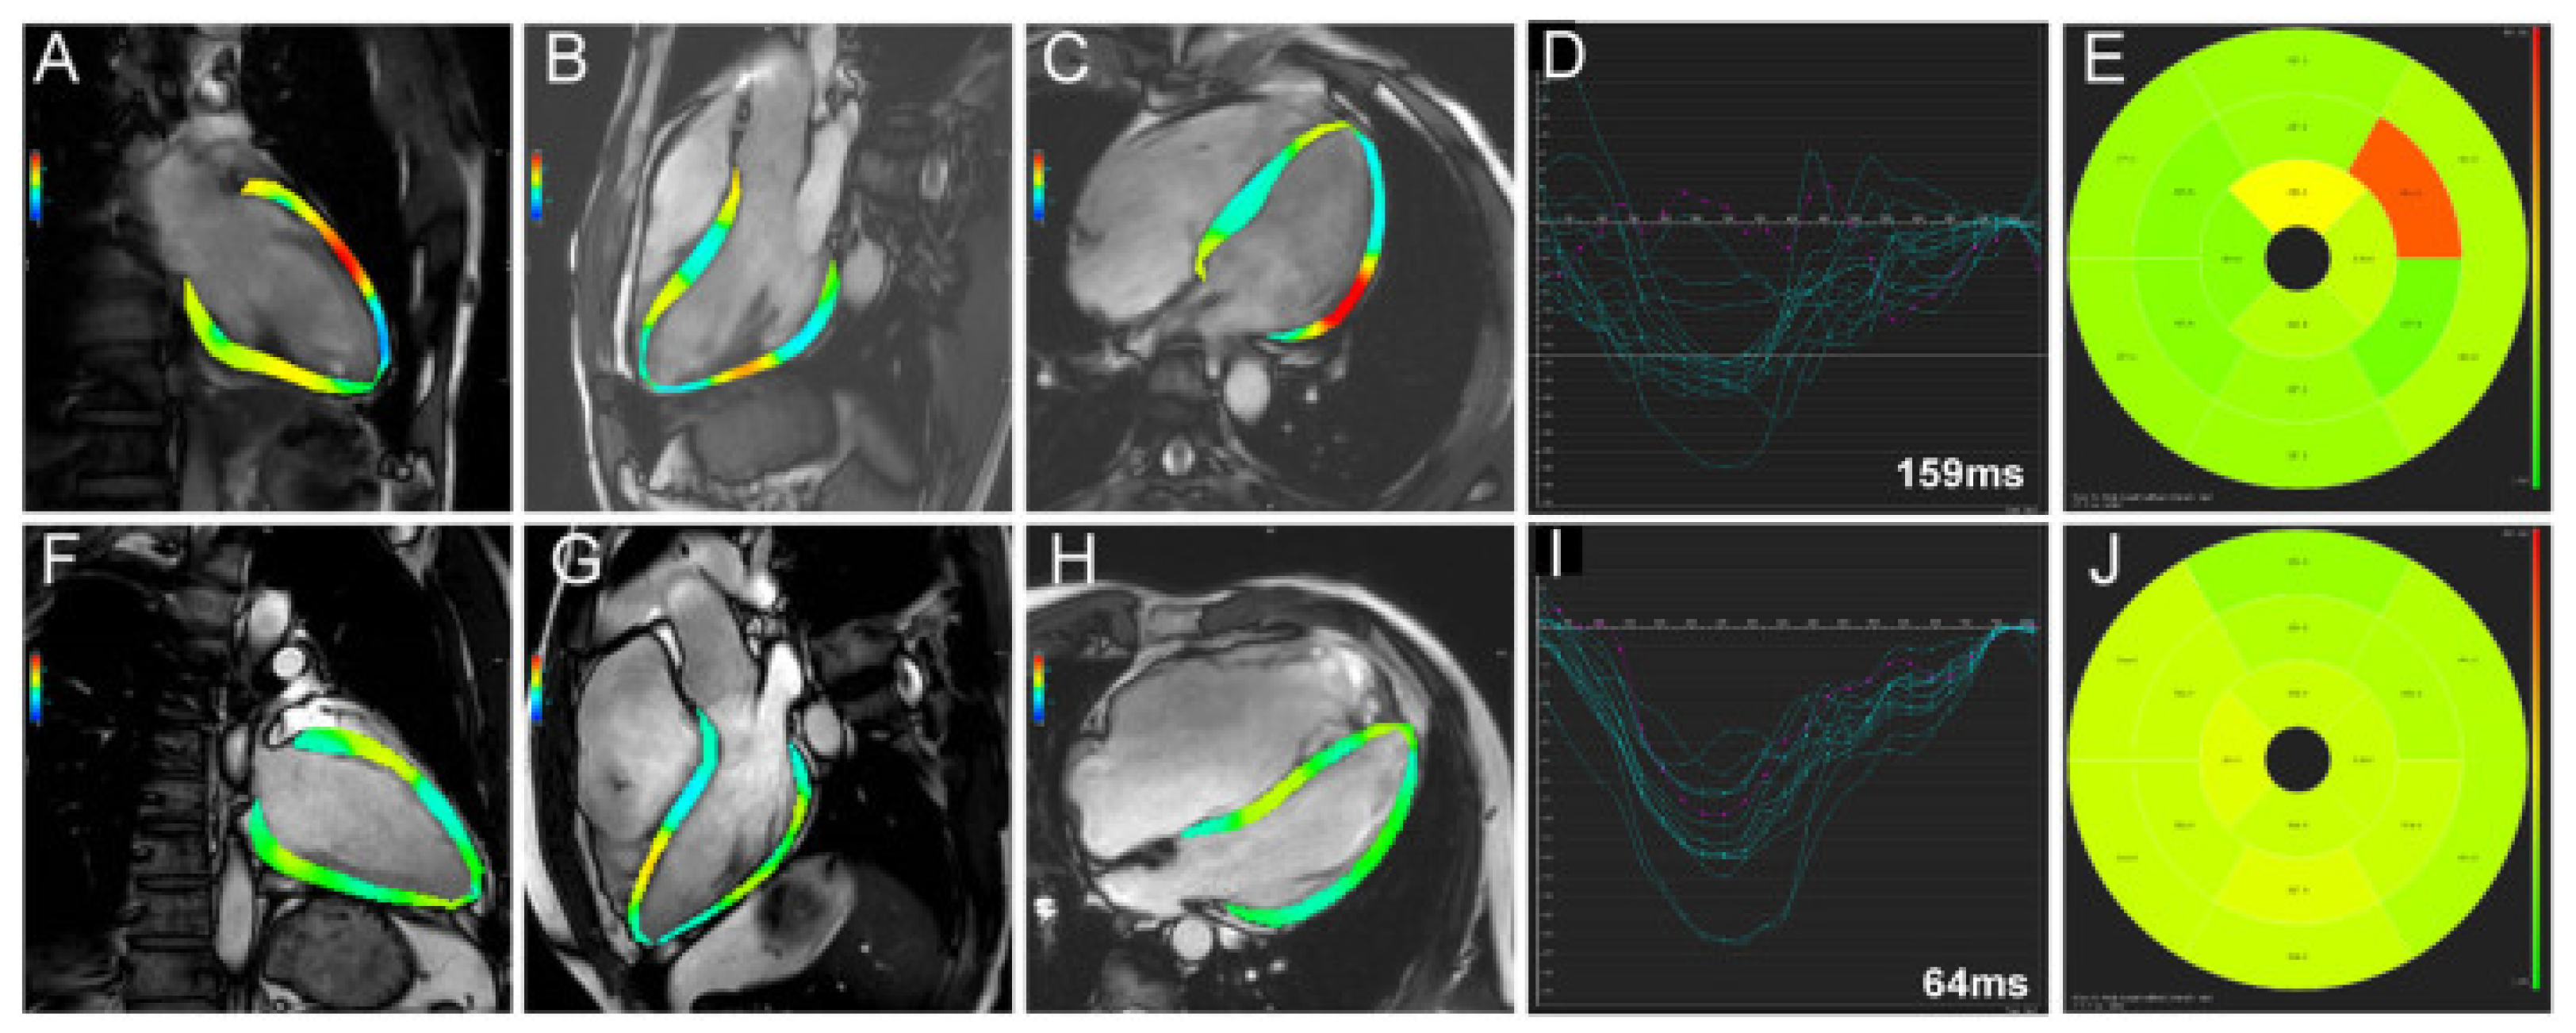

- Larsen, C.K.; Smiseth, O.A.; Duchenne, J.; Galli, E.; Aalen, J.M.; Lederlin, M.; Bogaert, J.; Kongsgaard, E.; Linde, C.; Penicka, M.; et al. Cardiac Magnetic Resonance Identifies Responders to Cardiac Resynchronization Therapy with an Assessment of Septal Scar and Left Ventricular Dyssynchrony. J. Clin. Med. 2023, 12, 7182. [Google Scholar] [CrossRef] [PubMed]

- Song, Y.; Chen, X.; Yang, K.; Dong, Z.; Cui, C.; Zhao, K.; Cheng, H.; Ji, K.; Lu, M.; Zhao, S. Cardiac MRI-derived Myocardial Fibrosis and Ventricular Dyssynchrony Predict Response to Cardiac Resynchronization Therapy in Patients with Nonischemic Dilated Cardiomyopathy. Radiol. Cardiothorac. Imaging 2023, 5, e220127. [Google Scholar] [CrossRef] [PubMed]